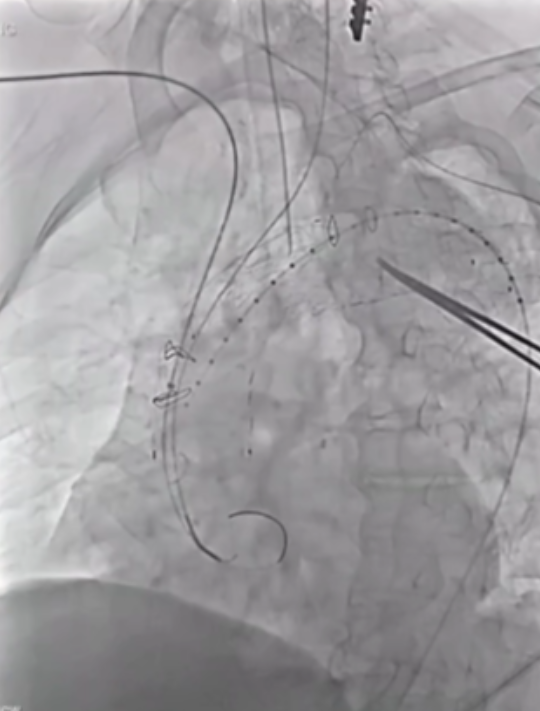

香港玛丽医院分享了38例主动脉弓分支支架植入病例的经验,其中28例为A/Br型,8例为B/Br型,1例为L型,患者平均年龄75.5岁,男性34例。30天死亡率为7.8%,手术中风率10.5%(2例严重+2例轻微),再干预率21%,逆行夹层3例,动脉瘤相关死亡2例。

此外,报告强调了健康主动脉的重要性,升主动脉直径<38mm是关键标准。曾有案例显示,在40mm主动脉植入支架后发生灾难性逆行A型夹层,这警示临床医生必须在健康主动脉段锚定,避免在夹层病理区域进行操作。

在主动脉介入治疗领域,支架设计持续创新。Terumo双分支支架采用大型矩形凹槽设计,即便旋转90度,仍能顺利接入分支,对于弓部曲线较为紧张的情况适配性更强。不过,该支架也面临技术挑战,手术中需要精准控制支架的旋转与对齐,以确保治疗效果。